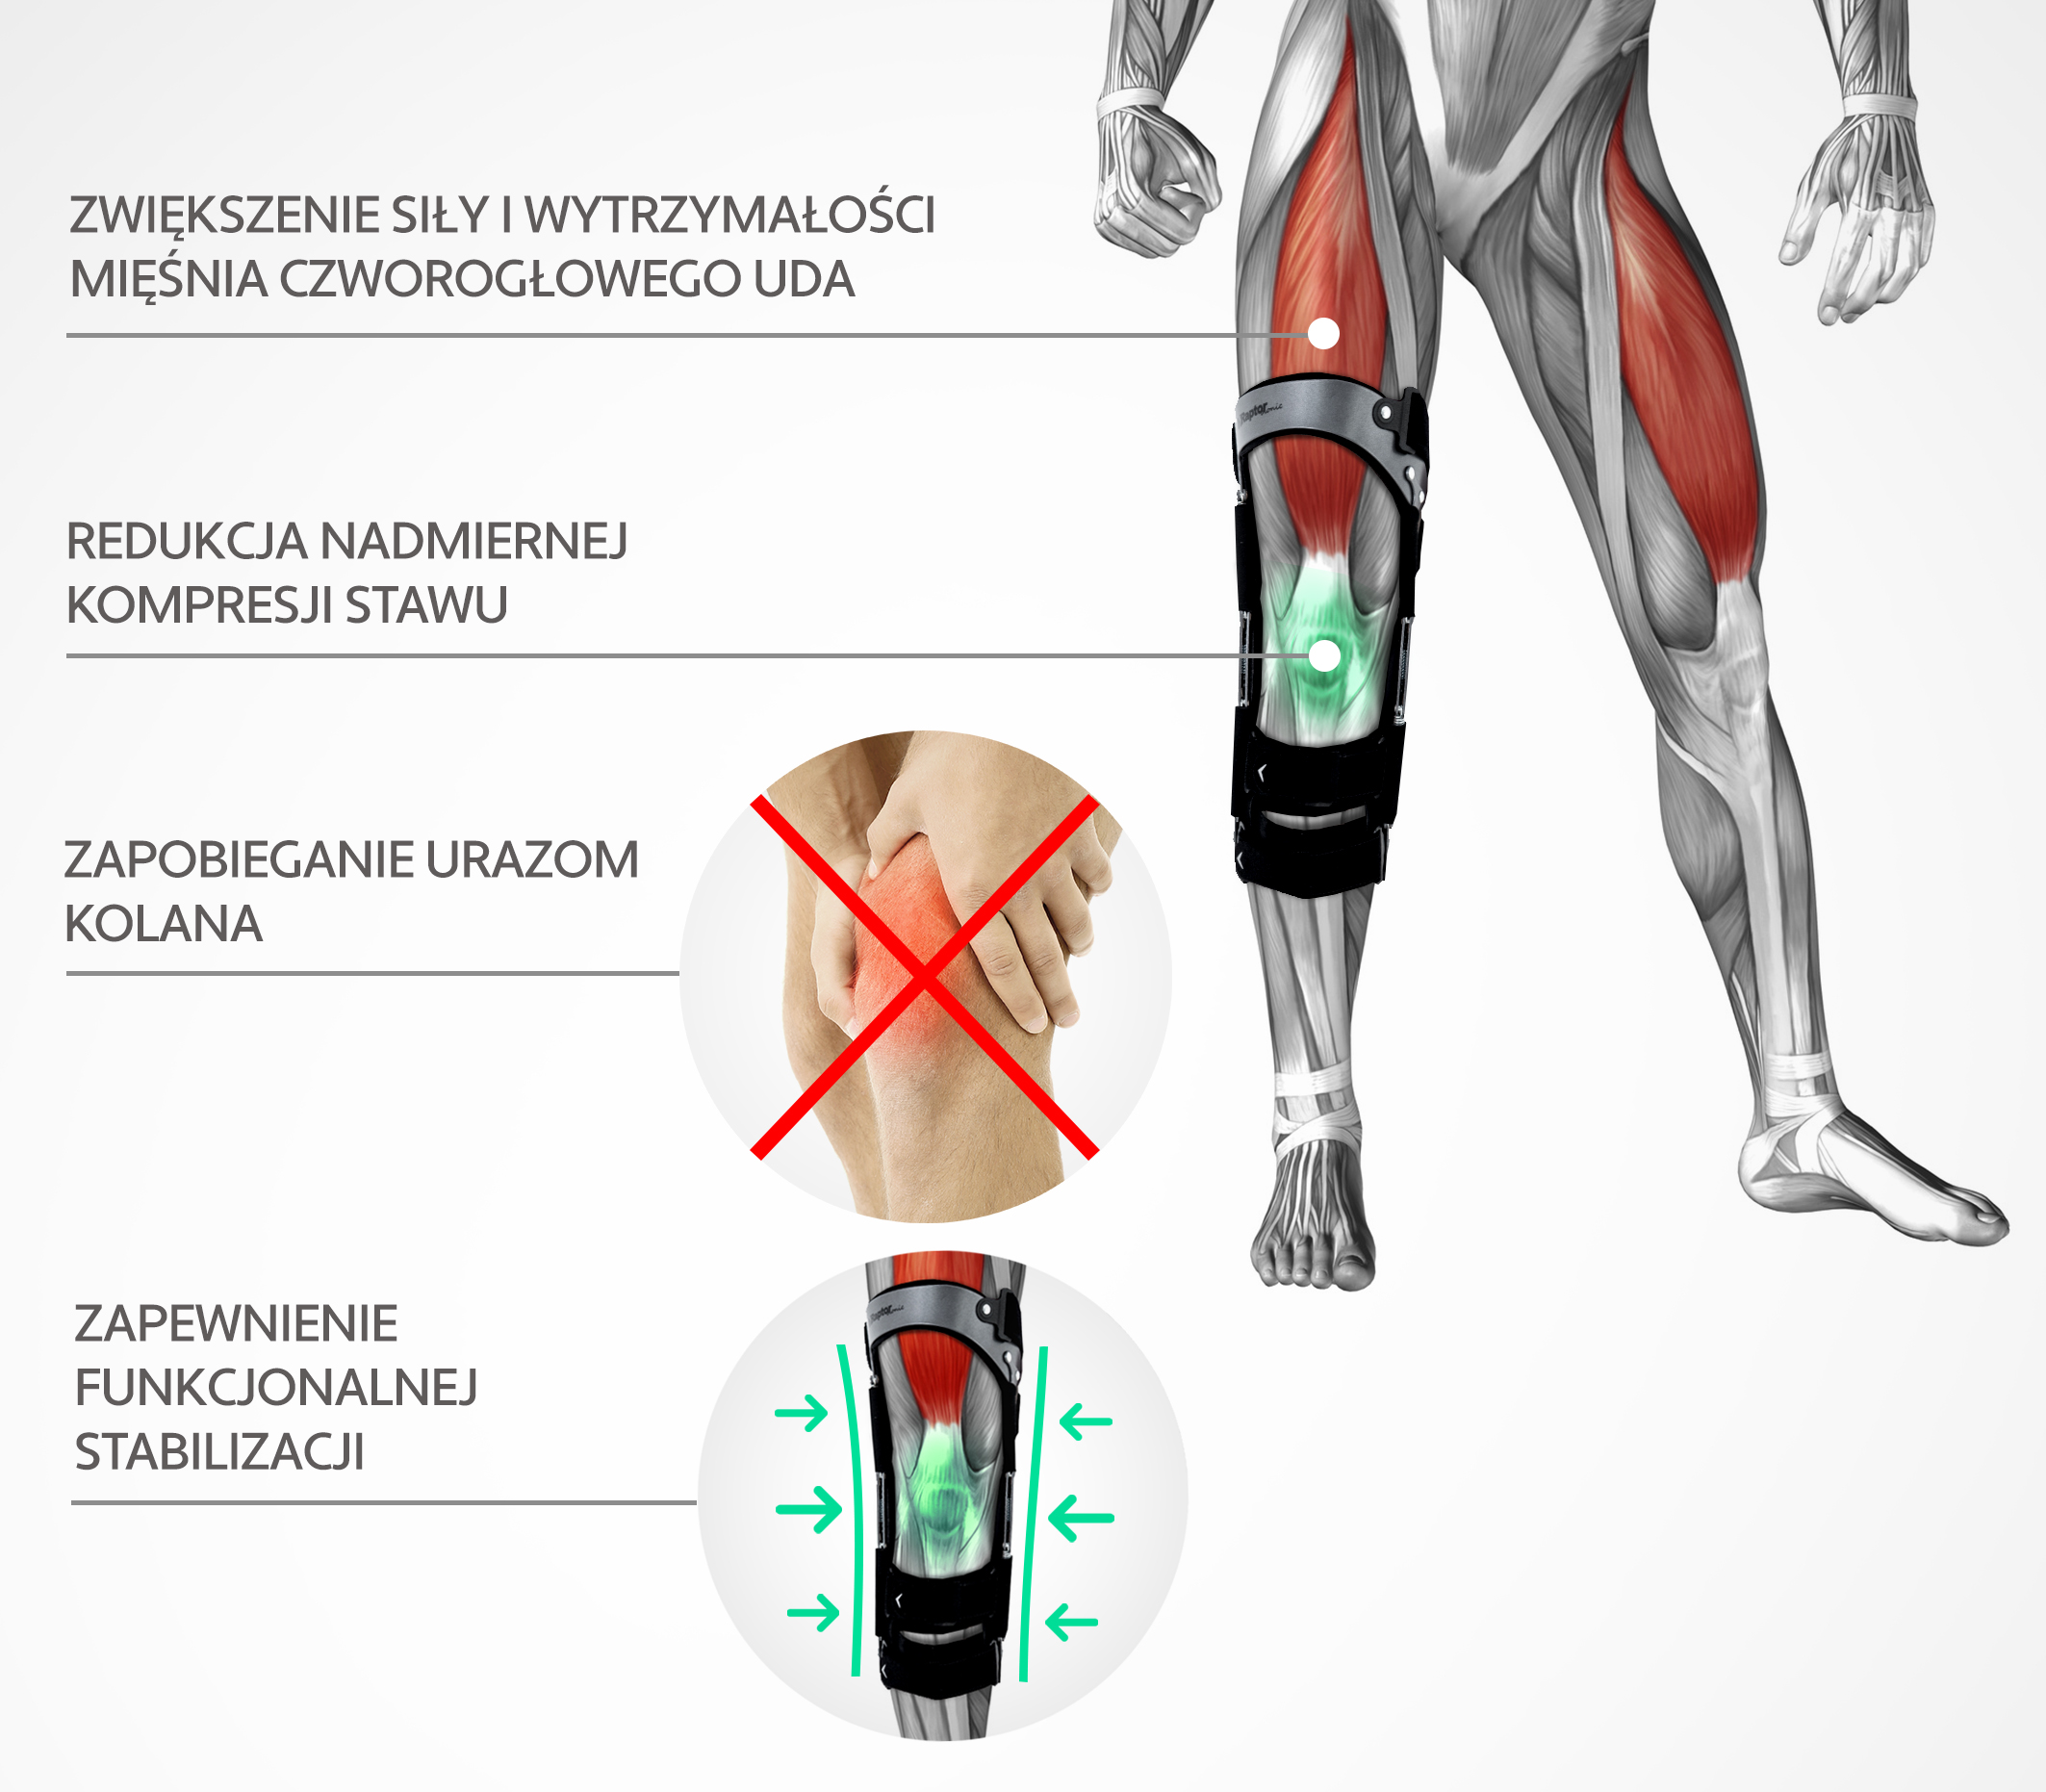

PRZEDNIO-TYLNA BIONICZNA ORTEZA KOLANA Z MECHANIZMEM SPRĘŻYNOWYM

RAPTOR BIONIC to coś więcej niż zwykła orteza ramowa kolana. Swoją innowacyjną bioniczną konstrukcję zawdzięcza zastosowaniu mechanizmu sprężynowego w zawiasach. Ma on na celu kumulację energii i przenoszenie obciążeń, wytwarzanych przez użytkownika w trakcie ruchu zgięciowego kolana, co znacząco odciąża staw kolanowy. W trakcie prostowania stawu, mechanizm wykorzystuje zmagazynowaną energię i wspomaga pracę prostowników kolana.

W rezultacie, orteza nie tylko stabilizuje staw kolanowy, ale dodatkowo zwiększa jego siłę i wytrzymałość.

System 4 punktów podparcia jest dynamicznym, najskuteczniejszym ze znanych, systemem zaopatrzenia stawu kolanowego.

System ten został opracowany w celu redukcji napięcia i ochrony kolana i w ortezie RAPTOR BIONIC rozkłada się następująco: 1-punkt przyłożony jest na przedniej stronie uda poprzez mocną aluminiową ramę. 2-punkt znajduje się na tylnej stronie łydki i oddziałuje na kończynę poprzez ramę. 3-punkt to taśma nadkolanowa zamocowana na tylnej stronie uda. 4-punkt to taśma mocująca na przedniej stronie podudzia, która wytwarza tzw. wstępne obciążenie (preload) na guzowatość kości piszczelowej (tuberositas tibiae) przesuwając kość piszczelową nieco do tyłu, co w efekcie daję zmniejszenie napięcia ACL.Warte podkreślenia jest słowo “zmniejszenie” – a nie całkowicie redukuje,

co wiąże się z korzystnym wpływem małych fizjologicznych napięć na gojące się więzadło krzyżowe. Badania z wszczepionym do więzadła urządzeniem pomiarowym wykazały znaczne zmniejszenie napięcia więzadła i to zarówno w pozycji siedzącej jak i stojącej, w porównaniu do kolana nie zaopatrzonego w aparat czteropunktowy.Skuteczność tego typu aparatów jest niezaprzeczalna. Chronią one staw kolanowy

przed uszkodzeniem podczas aktywności codziennej i sportowej. Przed operacją minimalizuje się w ten sposób ryzyko dodatkowych uszkodzeń tkanek miękkich, a po zabiegu otrzymujemy zabezpieczenie przeszczepu na cały okres jego remodelingu/przebudowy (ok.12-18 miesięcy). W trakcie rehabilitacji 4-punktowa stabilizacja pozwala na bardziej „agresywne leczenie” chroniąc więzadło wraz z osłabionym miejscem jego wszczepienia.Badania kliniczne wskazują, że ortezy z systemem 4 punktów podparcia 4P pomagają chronić ACL przed rozciągnięciem. Zarówno podczas obciążania jak i nieobciążania nogi, aparaty

z systemem 4P znacząco zmniejszały napięcie ACL jako kontrreakcja w stosunku do sił skierowanych ku przodowi. Dla przykładu: w sytuacji obciążenia aparat systematycznie redukował napięcie więzadła krzyżowego przedniego o 50%.Największymi zaletami ortez ortopedycznych z technologią 4P jest to że:

1. zmniejszają one napięcie ACL, co jest szczególnie ważne w czasie rehabilitacji podczas remodelowania się przeszczepu, 2. skracają one czas przebywania stawu w pozycji submaksymalnego wyprostu lub w tzw. pozycji „niebezpiecznej”, 3. zwiększają siłę nacisku na piszczel ku tyłowi, aby zapobiec jej przedniemu przesunięciu, 4. eliminują szok wyprostny odczuwany przez pacjenta w ostatniej fazie wyprostu kolana, w 100% zapobiegają zerwaniu więzadeł ACL.Właściwości redukujące napięcia ACL naszych ortez z technologią 4P, są istotne w procesie rehabilitacji oraz całego okresu remodelingu, czyli naturalnej przebudowy przeszczepu ACL. Poprzez stosowanie ortez z systemem 4-punktowym uzyskujemy też zdecydowaną redukcję potencjalnego luzu przeszczepu, szczególnie w przypadkach intensywnej rehabilitacji i treningu. Ortezy te stanowią niezaprzeczalnie bardzo mocną ochronę więzadeł stawu kolanowego. Przeznaczone są w szczególności dla osób uprawiających sporty o podwyższonym ryzyku urazów więzadła ACL. Zapewniają maksymalne poczucie bezpieczeństwa i najpewniejszą ochronę kolana.

ZALETY RAPTOR BIONIC: